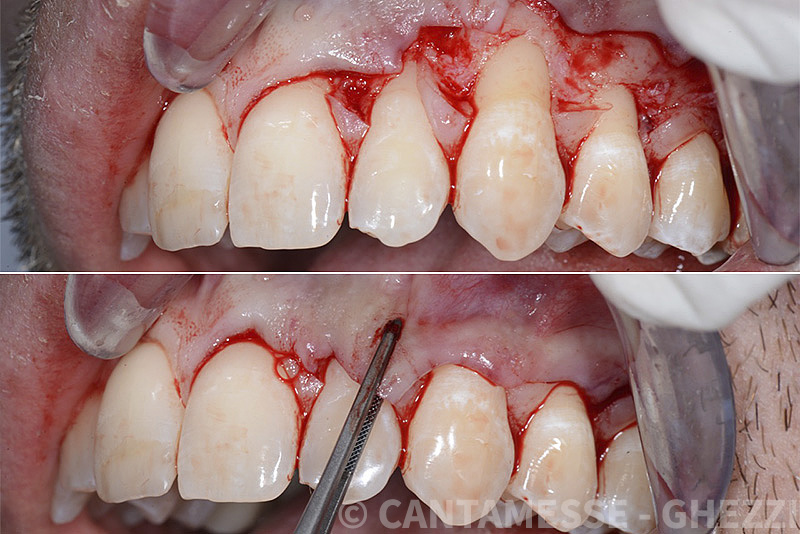

PREMESSA: in seguito all’estrazione dell’incisivo laterale superiore di destra, resasi necessaria per cause batteriche, si decide di affrontare il caso con il posizionamento di un impianto in sostituzione dell’elemento mancante dopo guarigione del sito infetto. Con tecniche rigenerative sia dei tessuti ossei mancanti a causa dell’infezione pregressa, sia dei tessuti gengivali che appaiono inizialmente troppo spostati in alto, si ripristina una corretta morfologia delle parabole (contorni) gengivali e delle papille interdentali (triangoli di gengiva tra due denti vicini).

Vengono utilizzati 2 tipi di provvisori: il primo, cementato ai denti vicini, viene utilizzato dal momento dell’estrazione del dente fino ad impianto osteointegrato (circa 6 mesi); il secondo, avvitato direttamente all’impianto, ha una funzione di prova estetica ma soprattutto di guida per la maturazione dei tessuti gengivali peri-implantari portandoli verso la maturazione completa prima di posizionare la corona finale in disilicato di litio.